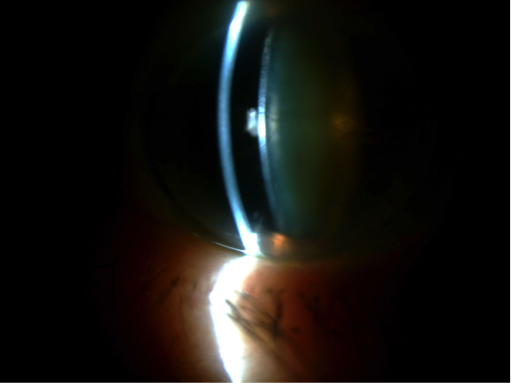

Otras circunstancias, como la debilidad zonular, pueden dificultar la cirugía, e incluso si esta es muy acusada llegar a imposibilitar el implante de la lente en el saco capsular y precisar de una segunda intervención para implantarla. En el último video, se ve como la catarata presenta una debilidad zonular, detectada intraoperatoriamente, que puede ser manejada con los mismos ganchos de iris manteniendo la capsula “in situ” y tensándola al final de la cirugía con un anillo de tensión capsular.